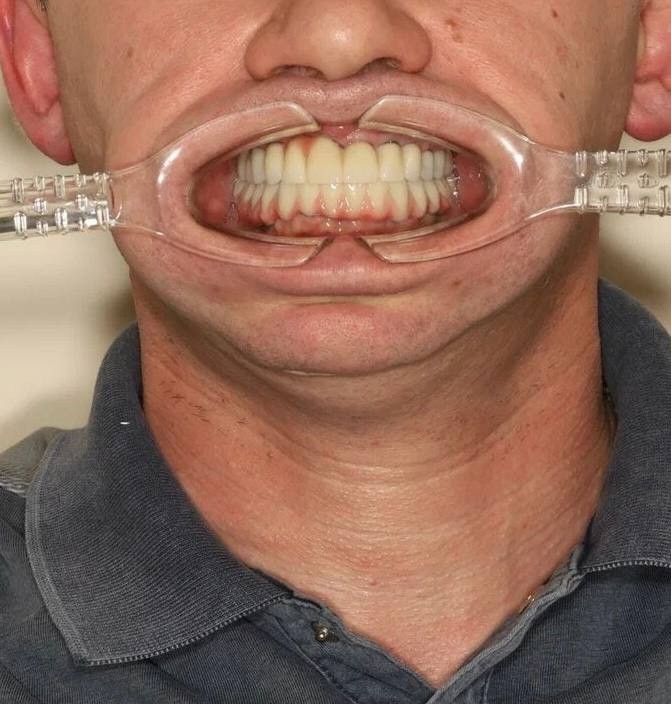

Фотографии до и после: Имплантация

На странице представлено портфолио стоматологий Самары с фото работ до и после имплантации зубов. Мы собрали разные клинические случаи: одиночные импланты, восстановление нескольких зубов и полная реконструкция зубного ряда. Здесь вы можете видеть, как выглядят восстановленные зубы, меняется форма улыбки после процедуры. Изучите результаты до и после имплантации зубов, чтобы оценить качество работы врачей и выбрать стоматологию в Самаре, которая поможет вернуть функциональность и эстетику вашей улыбке.

Имплантация All-on-4

Имплантация All-on-4

Имплантация All-on-4

Имплантация All-on-4

Имплантация All-on-4

Имплантация All-on-4

Имплантация All-on-4

Имплантация All-on-4

тотальная реабилитация пациента по методике All-on-4

Имплантация All-on-4

тотальная реабилитация пациента по методике All-on-4

Имплантация All-on-4

тотальная реабилитация пациента по методике All-on-4

Имплантация All-on-4

тотальная реабилитация пациента по методике All-on-4